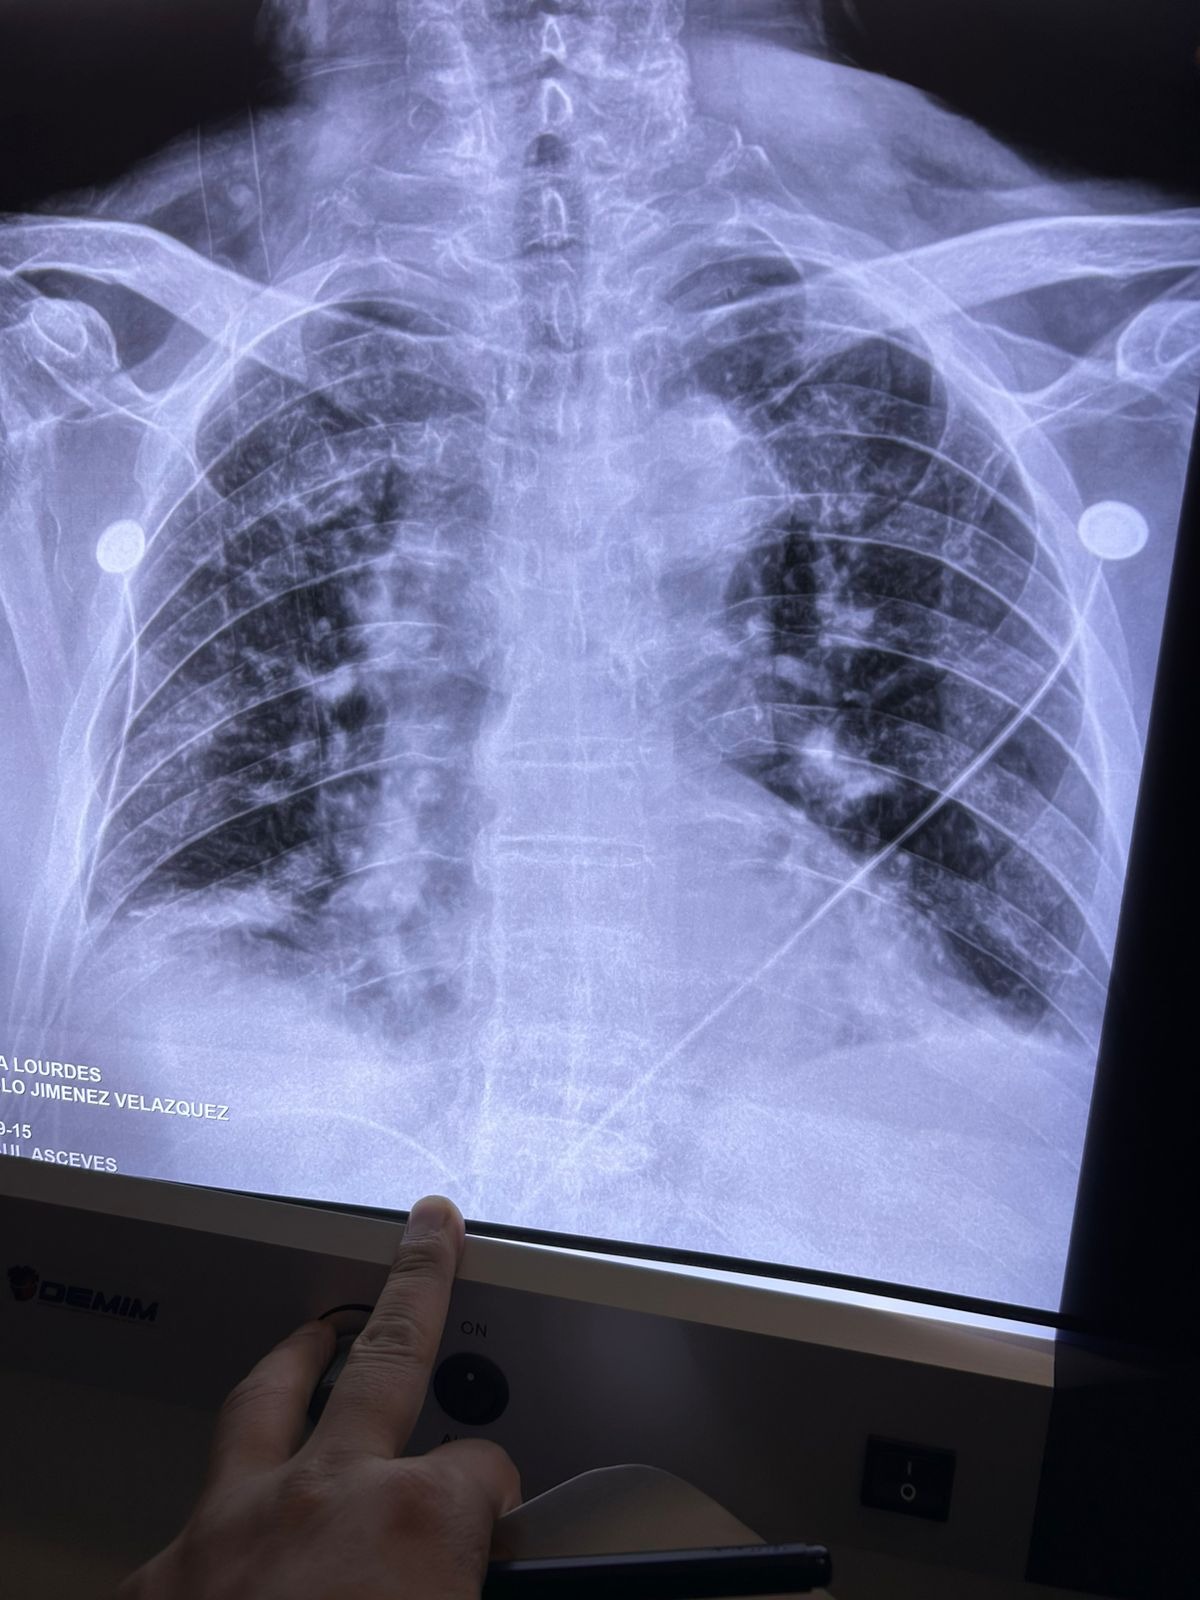

Grandpa has been battling pneumonia for the past two weeks. He’s already undergone two major surgeries—one to place a feeding tube and another to help him breathe. Despite all of this, his recovery has been slow, and we’re still waiting for signs of improvement.

Mi abuelo lleva dos semanas luchando contra una neumonía. Ya se ha sometido a dos cirugías importantes: una para colocarle una sonda de alimentación y otra para ayudarle a respirar. A pesar de todo esto, su recuperación ha sido lenta y seguimos esperando señales de mejoría.